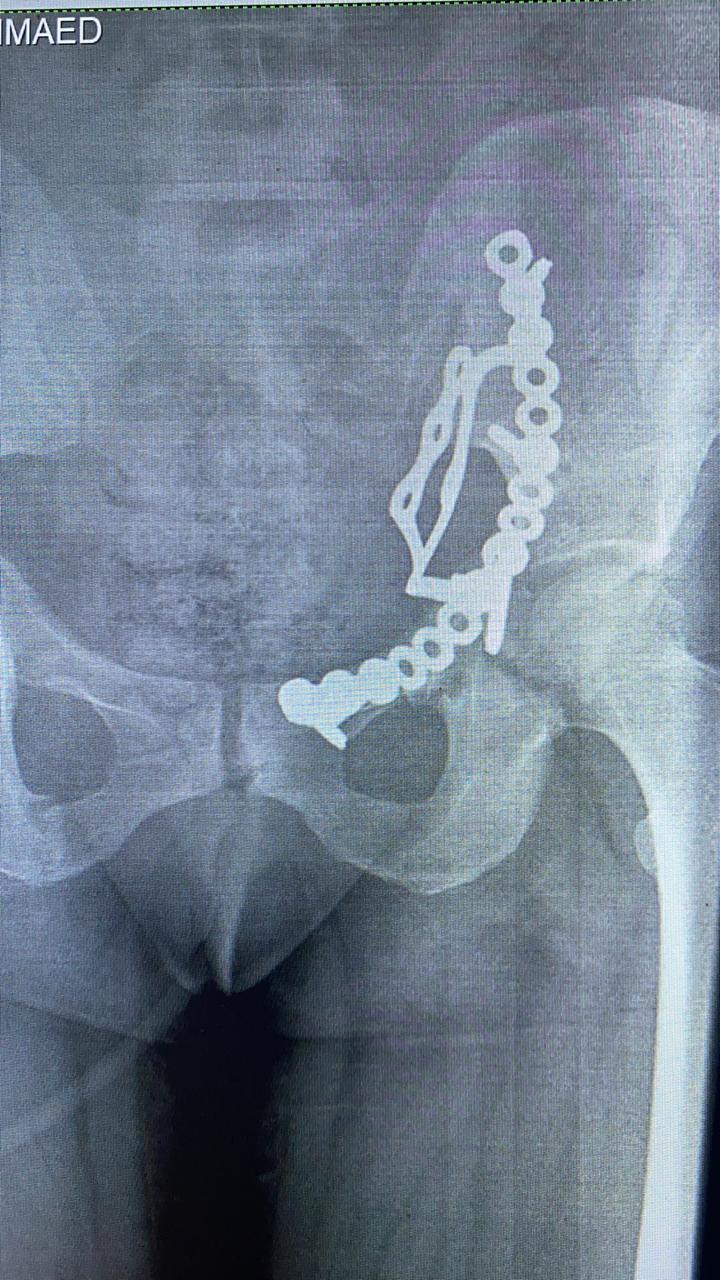

قام الفريق الطبي بقسم جراحة العظام بمستشفي أبوحماد المركزي، تحت إشراف مدير المستشفى، بإجراء عملية رد مفتوح مع تثبيت داخلي لكسر مفتت بالحق الحرقفي لعظم الحوض لسيدة، من خلال جراحة فتح البطن والحوض باستخدام شريحة من نوع خاص تحت مخدر عام بالعمليات...

تعد العملية ذات طابع خاص، وذلك بعد دخول المريضة قسم الإستقبال والطوارئ، إثر ادعاء حادث مروري، حيث تم إجراء كافة الفحوصات اللازمة وتبين اصابة المريضة بجرح بالمثانة نتج عنه بول دموي ووجود كسر مفتت بالحق الحرقفي لعظم الحوض، والمريضة الآن في حالة جيدة ومستقرة تحت متابعة الأطباء بالمستشفى...